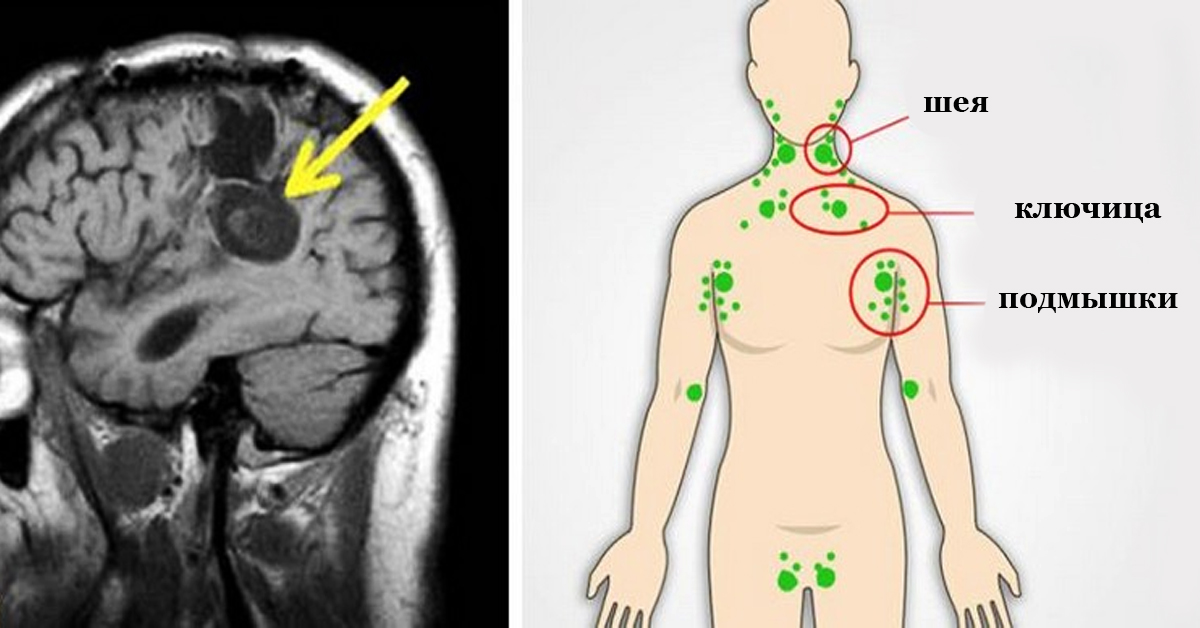

Вот, что провоцирует и ускоряет рост клеток рака в нашем теле! Узнай лучшие способы, чтобы остановить это!